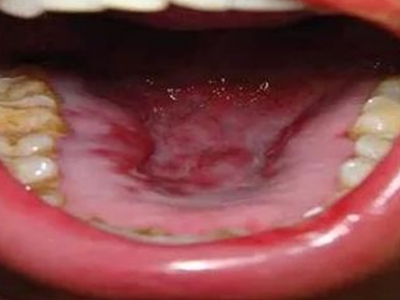

艾滋病皮肤肿瘤是由于艾滋病患者的人体免疫系统被破坏,造成人体免疫功能严重低下,从而引发各种肿瘤。在艾滋病皮肤肿瘤中,常见的有卡波西肉瘤、淋巴瘤、恶性黑色素瘤及鳞状细胞癌。

艾滋病可侵袭皮肤黏膜,引起卡波西肉瘤、淋巴瘤、恶性黑色素瘤及鳞状细胞癌等皮肤肿瘤,具体表现有所差异。

卡波西肉瘤引起的皮损开始为粉红色斑疹,长轴与皮纹方向一致,以后颜色变暗,形成淡紫色或棕色的斑疹或斑块,最后变为出血性皮损和结节。